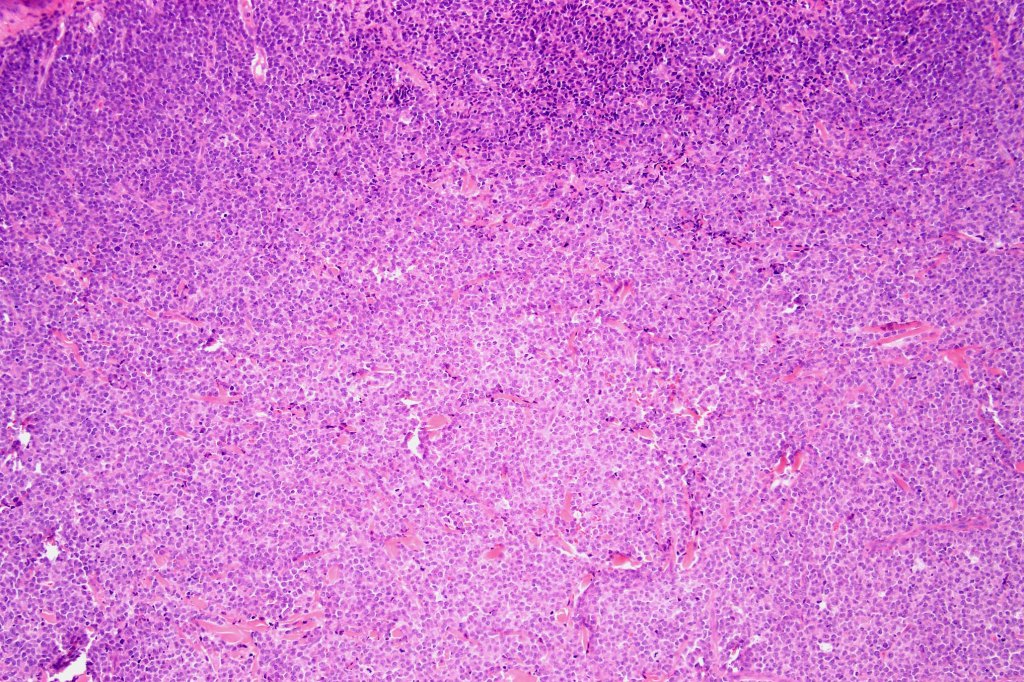

Histological features

. Dermal +/- subcutaneous fat infiltrate

. No angioinvasion or angiodestruction

. Monotonous blast cells with gray-blue cytoplasm & irrregular vesicular nuclei with prominent nucleoli